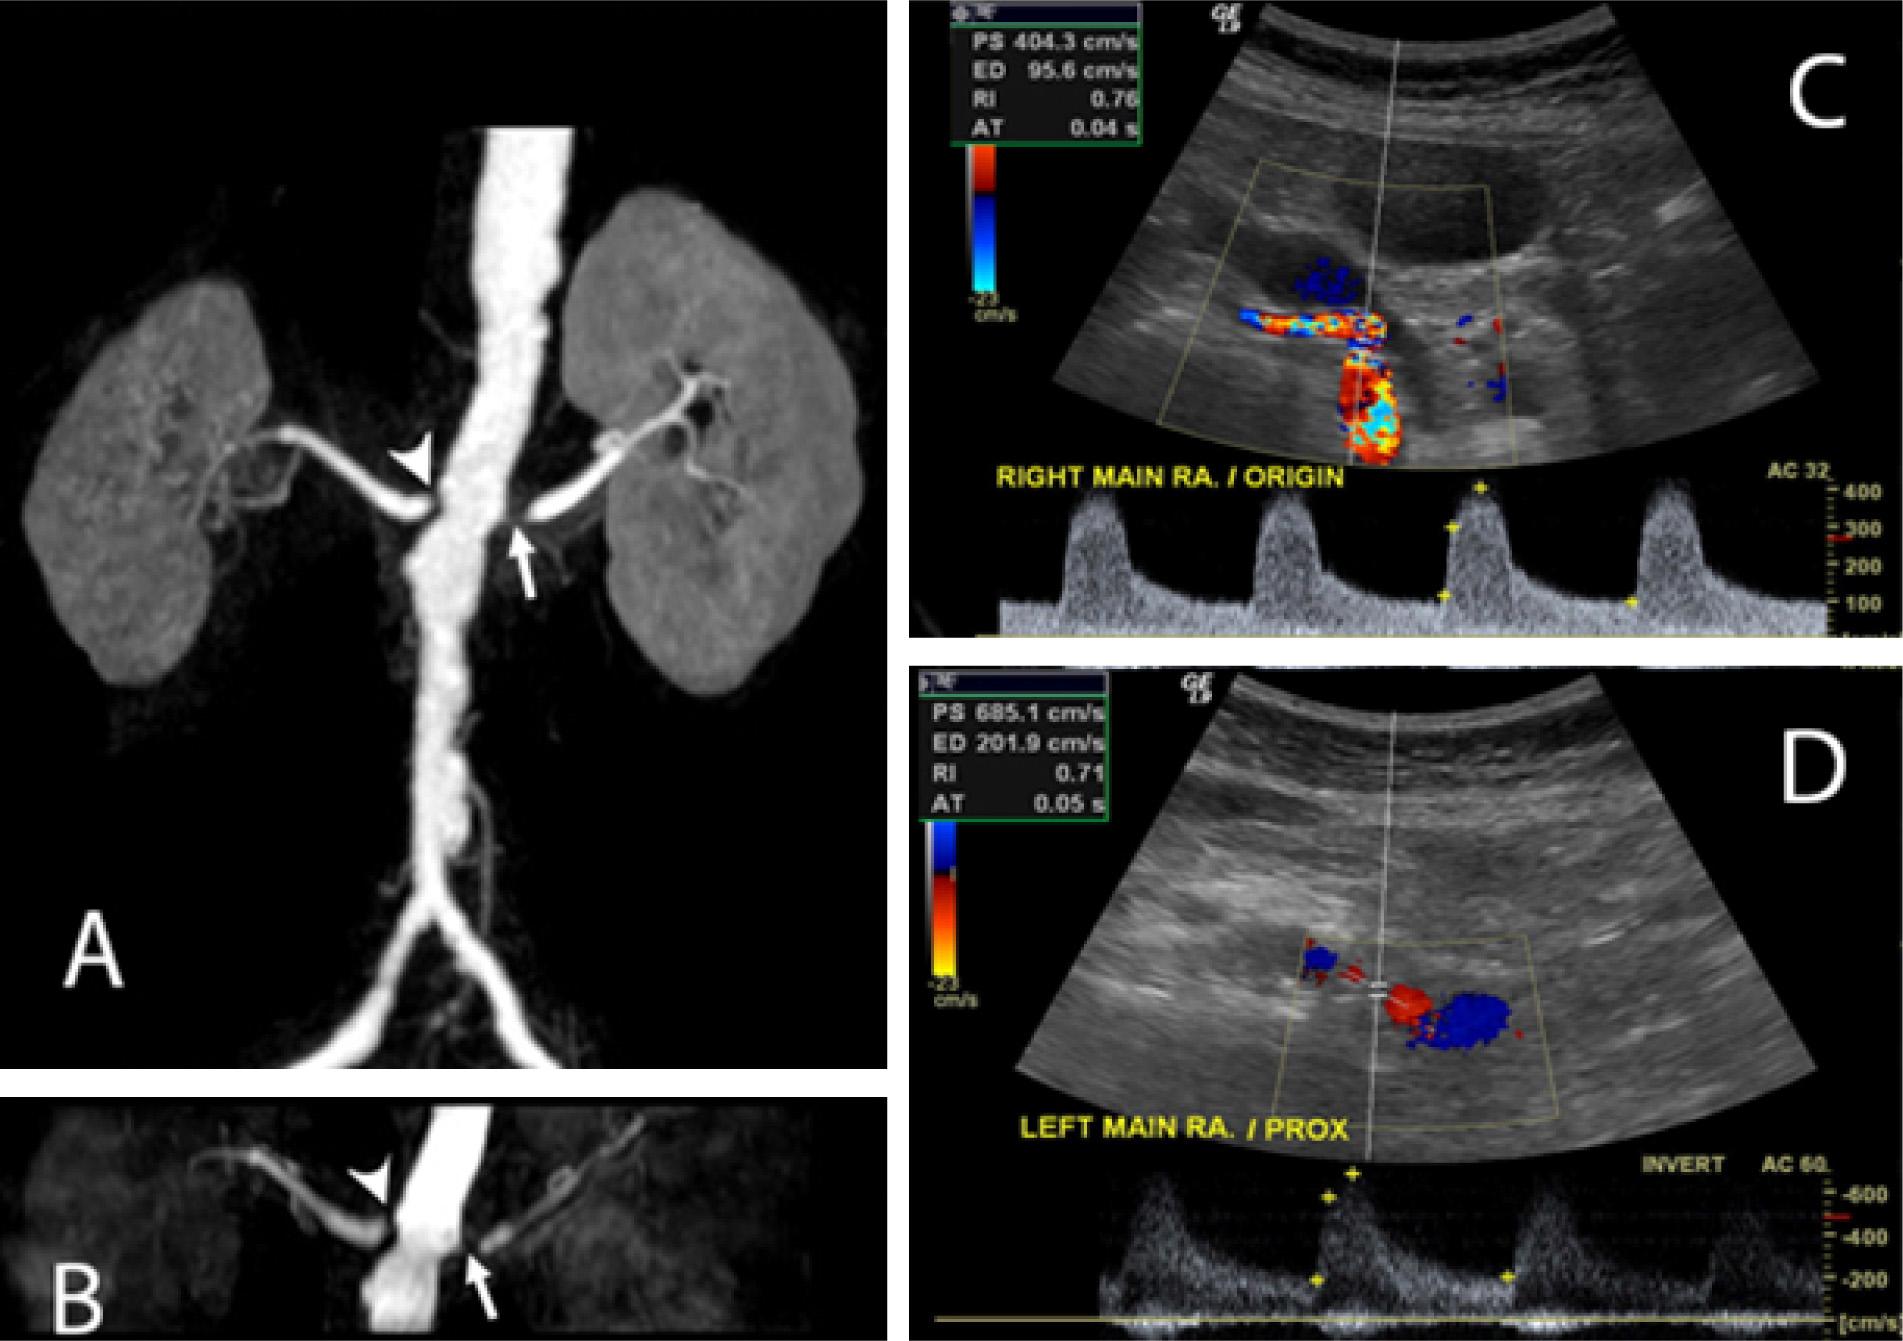

Figure 1

Severe bilateral renal artery stenosis was diagnosed in an 80-year-old patient. Arrow heads and arrows show severe renal artery stenosis at the proximal right and left main renal arteries in both contrast-enhanced magnetic resonance angiography (MRA) (A) and noncontrast enhanced MRA (B). Color Doppler ultrasound of right and left main renal arteries (C and D) showed aliasing color and high peak systolic velocities, indicating severe renal artery stenosis.